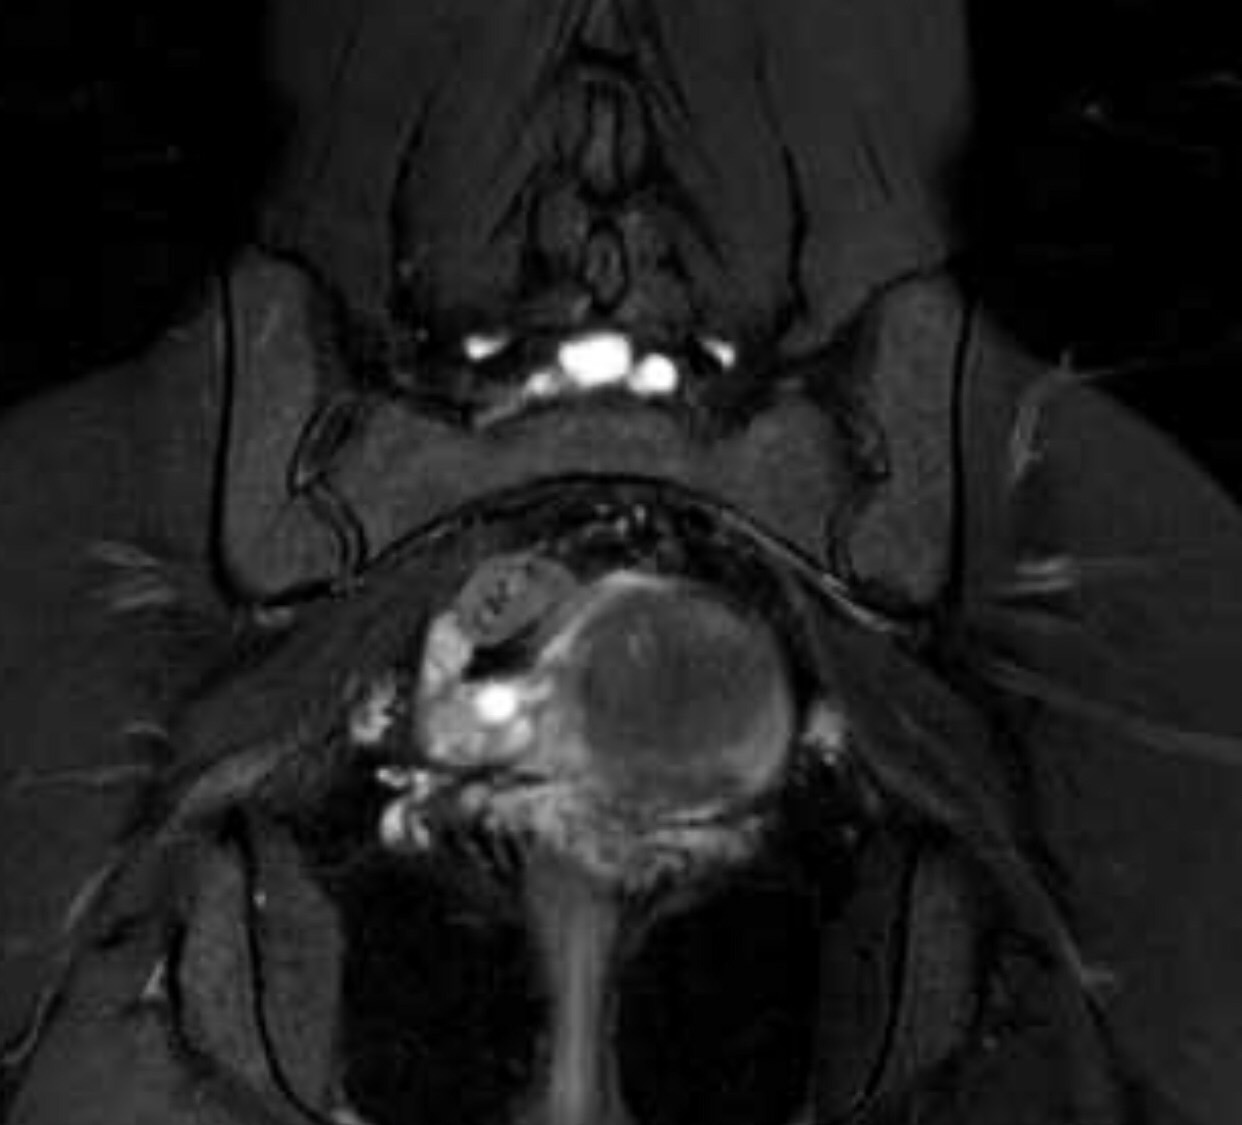

มีใครช่วยดูภาพ MRI Pelvis ของเราได้ไหมค่ะ

เรามีอาการทางประสาท ปวดแสบปวดร้อนที่กล้ามเนื้อขาอ่อน ชาขาลงเท้าเป็นบางครั้ง ส่วนมาจะเจ็บๆคันเหมือนโดนมดแดงไฟกัด บริเวณขาอ่อนด้านใน บางทีก๋กล้ามเนื้อสะโพกกับขาหนีบล็อกหกเกร็ง สะโพกรู้สึกหกเกร็งขาดความยืดหยุ่นเหมือนหนังยางที่ยึดแล้วมันปริแตกเป็นริ้ว เพราะหมดสภาพ บางทีก็แสบบริเวณกล้ามเนื้อเหนือหัวเข่า เรากำลังตามหาผู้ใจบุณช่วยวิเคราะห์ผล MRI ให้เราได้หลังไมค์มาเลนค่ะ เรายินดีส่งไฟล์ที่เป็น Full Version ให้ทางไลน์

จากรูปจุดขาวๆก้อนเล็กคืออะไรค่ะ